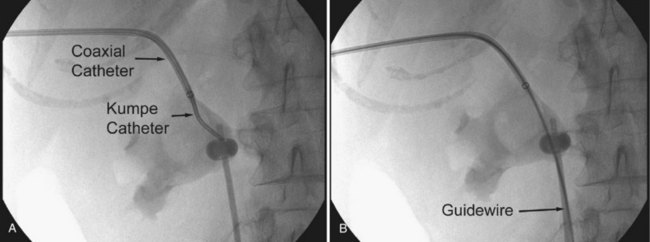

There are several techniques for getting a guidewire down the ureter. The safest maneuver is to place a stiff angled-tip hydrophilic guidewire adjacent to the initial stiff angled-tip hydrophilic guidewire using a coaxial or dual-lumen catheter. Remove the coaxial or dual-lumen catheter and place an angled tip catheter (Kumpe, Cobra, or coudé tip) over the angled-tip hydrophilic guidewire to help direct it down the ureter. Once the stiff angled-tip hydrophilic guidewire is down the ureter, optimally all the way into the bladder, use the coaxial or dual-lumen catheter to place a second guidewire down the ureter. In cases of secure access, the initial wire can be exchanged for a stiff angled-tip hydrophilic guidewire through an angled tip catheter to get down the ureter right away (Fig. 47–22); alternatively, the surgeon can use a stiff angled-tip hydrophilic guidewire as the initial wire.